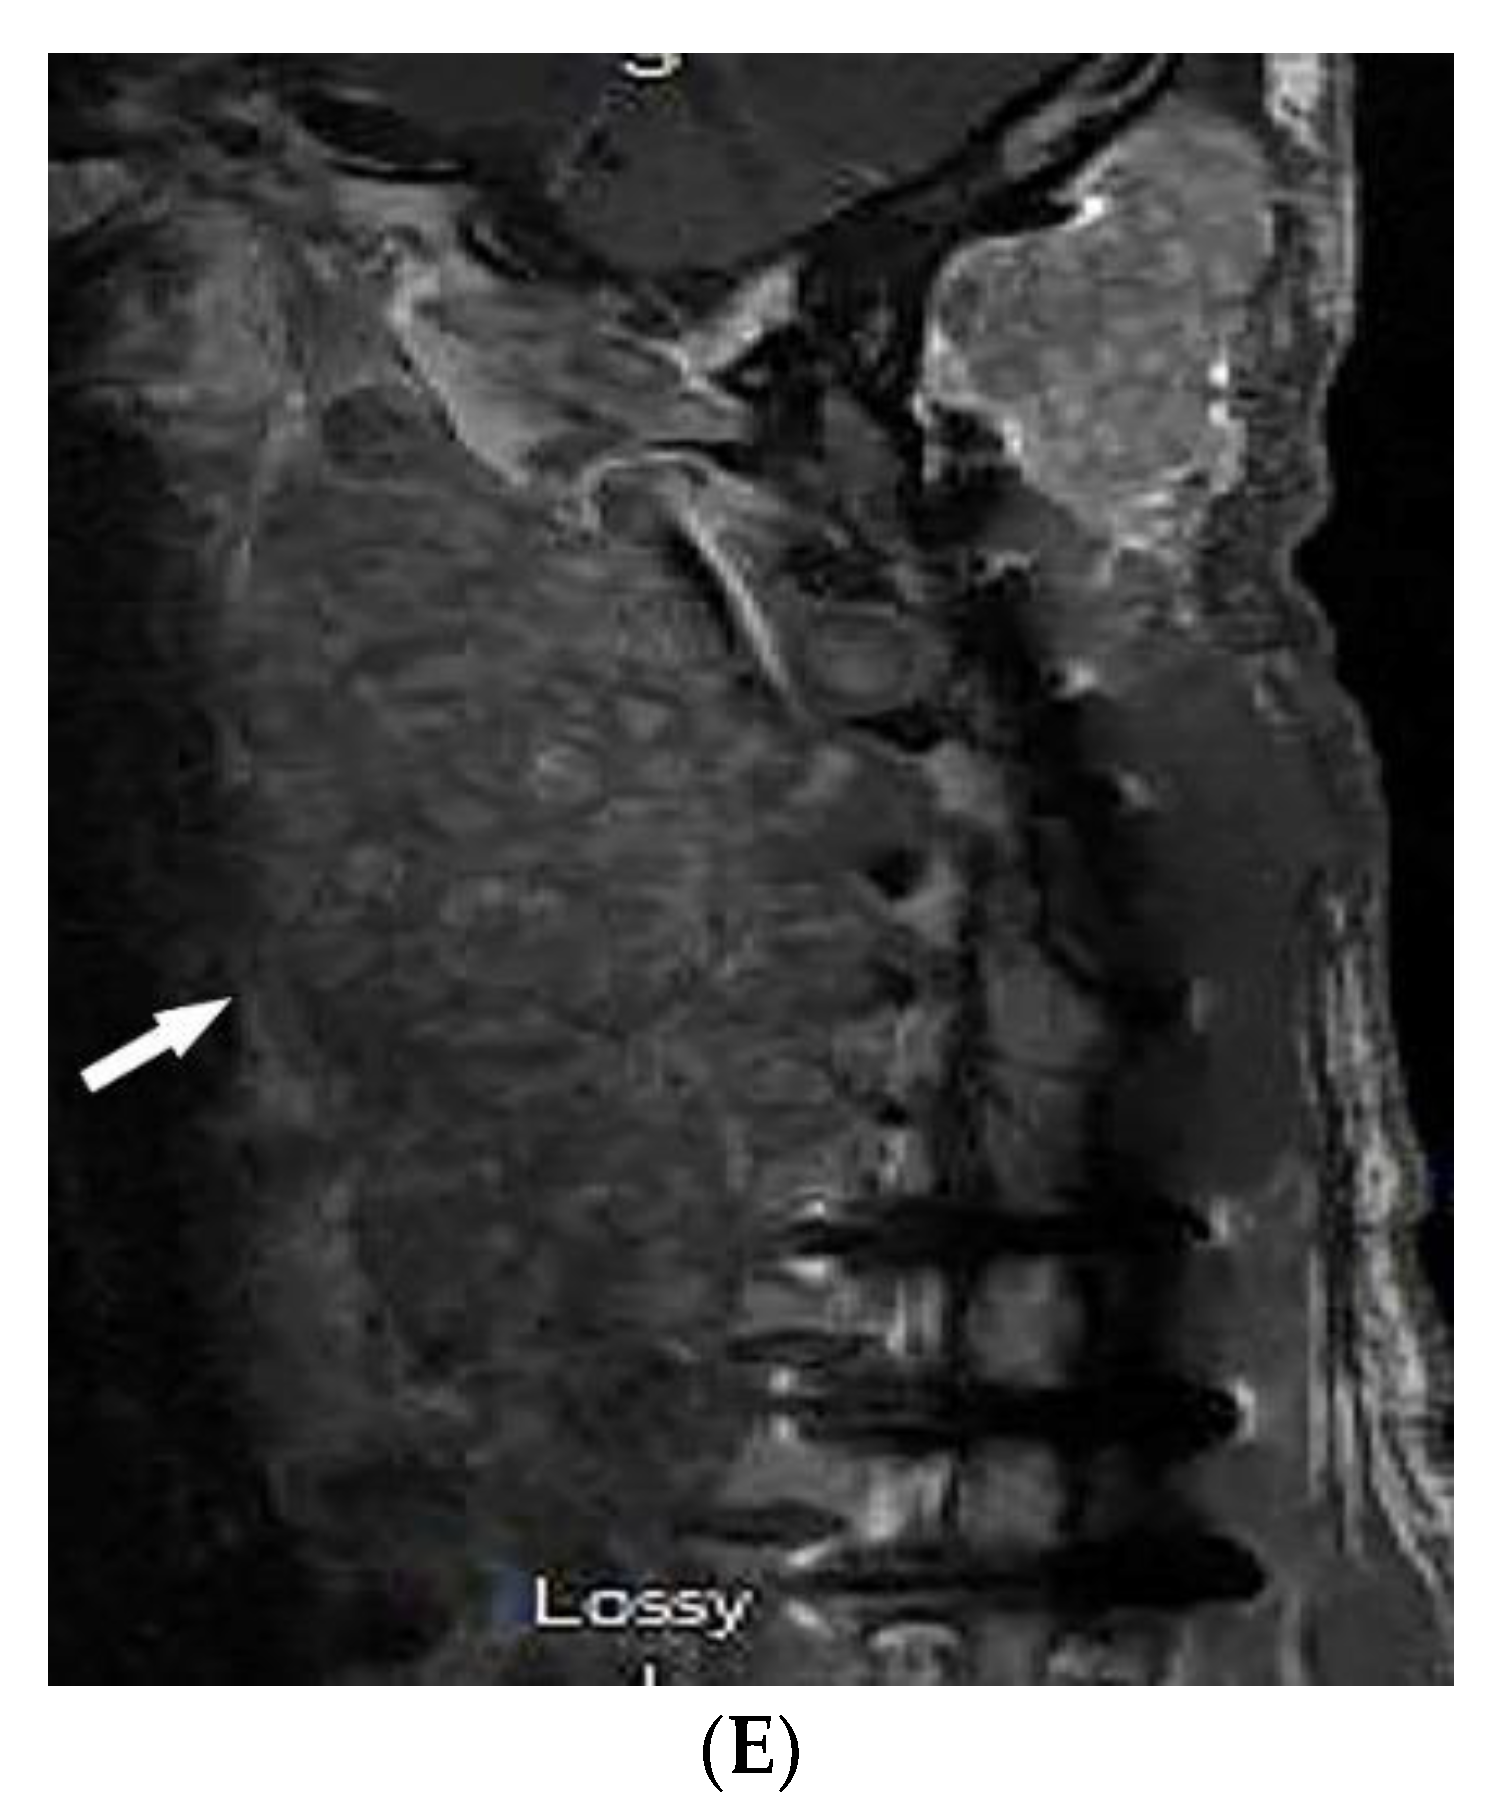

3.11. Buschke–Ollendorff Syndrome

| Buschke–Ollendorff syndrome | Dermatofibrosis lenticularis disseminata Osteopoikilosis Melorheostosis | Bony islands and multiple sclerotic lesions cause mottled appearance Cortical thickening with undulating bone |